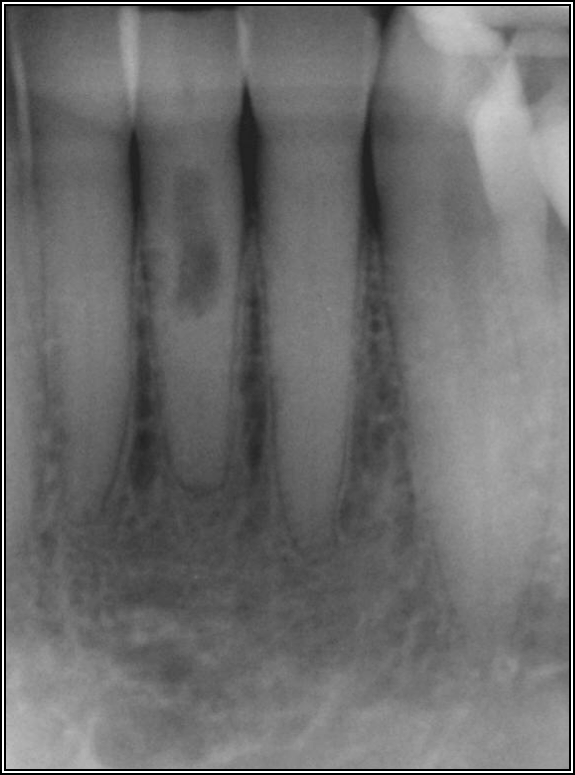

Fig 25. The case at first may appear to be good.

Figure 25

Fig 26. A further look shows the situation is more complex.

Figure 26

Finally, it is important to think in the 3-dimensional (3D). Most observers may believe the case in Figure 25 looks good, ignoring the root-canal access. From Figure 26, one can see that the situation actually is not ideal—about 20% may be filled, meaning that 100% is not clean. When viewing radiographs, it is common to consider them from the incomplete perspective shown in Figure 25. If a patient is experiencing sensitivity seemingly inexplicably, it may be useful to view the tooth in 3D with CBCT—the true dimensions of the tooth should be considered.